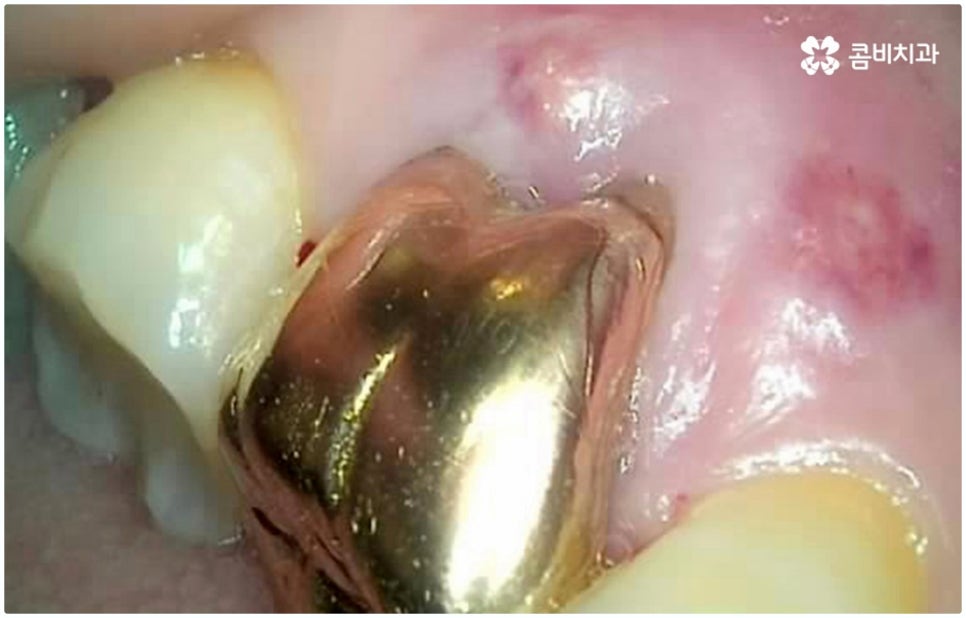

예를 들어 충치가 악화되어 세균이 치아 내부 치수 조직까지 침투한 경우 감염된 신경을 깨끗하게 제거하고 신경관 내부를 생체친화 충전재로 밀봉한 후 크라운으로 덮어 씌워주는 신경치료를 하게 되는데, 이때 감염 부위가 제대로 제거되지 않거나 2차 감염이 일어나 손상이 치아 뿌리까지 진행되면 자연 치아를 살리는 게 어려워 질 수 있습니다. 시기를 놓치면 재신경치료, 치근단 절제술 등의 보존 치료 역시 소용이 없어질 수 있으니 만약 신경 치료를 받은 치아가 있다면 더욱 신경써서 위생 관리에 주의하시고 검진을 통한 관리를 게을리 하지 않으시길 권유드리고 있어요.

물론 타고난 치아만큼 편안하게 사용하기는 어려우므로 치아 상실에 이르기 전에 자연 치아를 살리는 방향으로 보존 치료를 해 주는 게 구강 건강을 유지하는데 보다 바람직한 방법이라고 할 수 있는데요. 하지만 이미 해당 치아가 치아로서의 기능을 상실했다면 발치하지 않고 그대로 둔다는 것이 더이상 의미가 없으며 오히려 시간이 지날수록 주변 치아나 잇몸까지 손상이 번질 수 있으니 상황에 따라 늦지 않게 올바른 대처를 해 줄 필요가 있어요